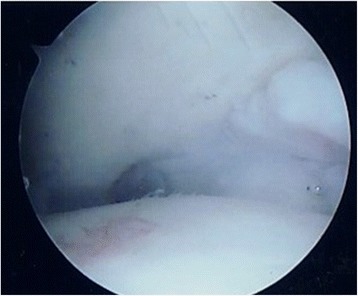

The first author (LO) performed all surgical procedures, under general anesthesia, in the supine position, with manual or temporary body traction of the ankle, without a tourniquet. A standard knee arthroscope and two standard anteromedial and anterolateral portals were used, switching to a 2.7 mm 30° angled arthroscope if needed. At arthroscopy, cartilage lesions were classified according to Outerbridge (Fig. 1). All the structures were palpated with a probe to assess osteochondral and bony features, and the presence of soft tissue impingement.

Fig. 1.

Arthroscopic view of grade IV cartilage lesion of the talus